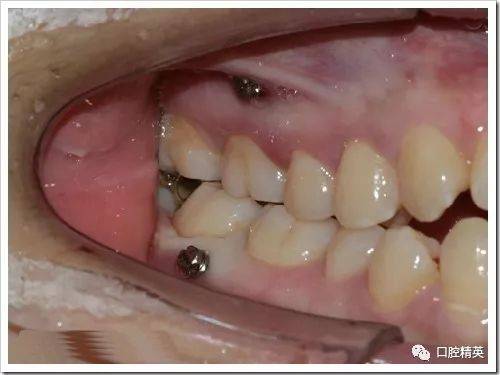

正畸微种植钉植入图片中,操作步骤、解剖结构识别与关键技术要点如何通过影像呈现?-图2

(图片来源网络,侵删)